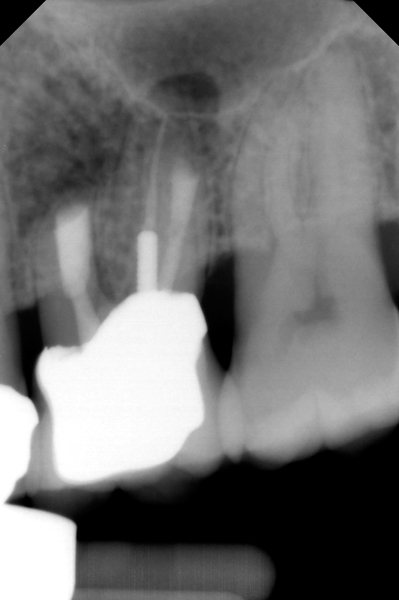

Fig 11. MTA perforation repair done, and calcium hydroxide medication placed in the canals.

Figure 11

Clinical procedure: Once a perforation occurs, the extent of the perforation must be assessed. If there is an adjacent bony defect, the bony defect should first be filled with an osteoconductive or osteoinductive material. This can be done with a bone graft, calcium sulfate, or collagen/gelatin sponge. The dentinal portion of the tooth that has been perforated is then restored with MTA (Figure 9 through Figure 14).